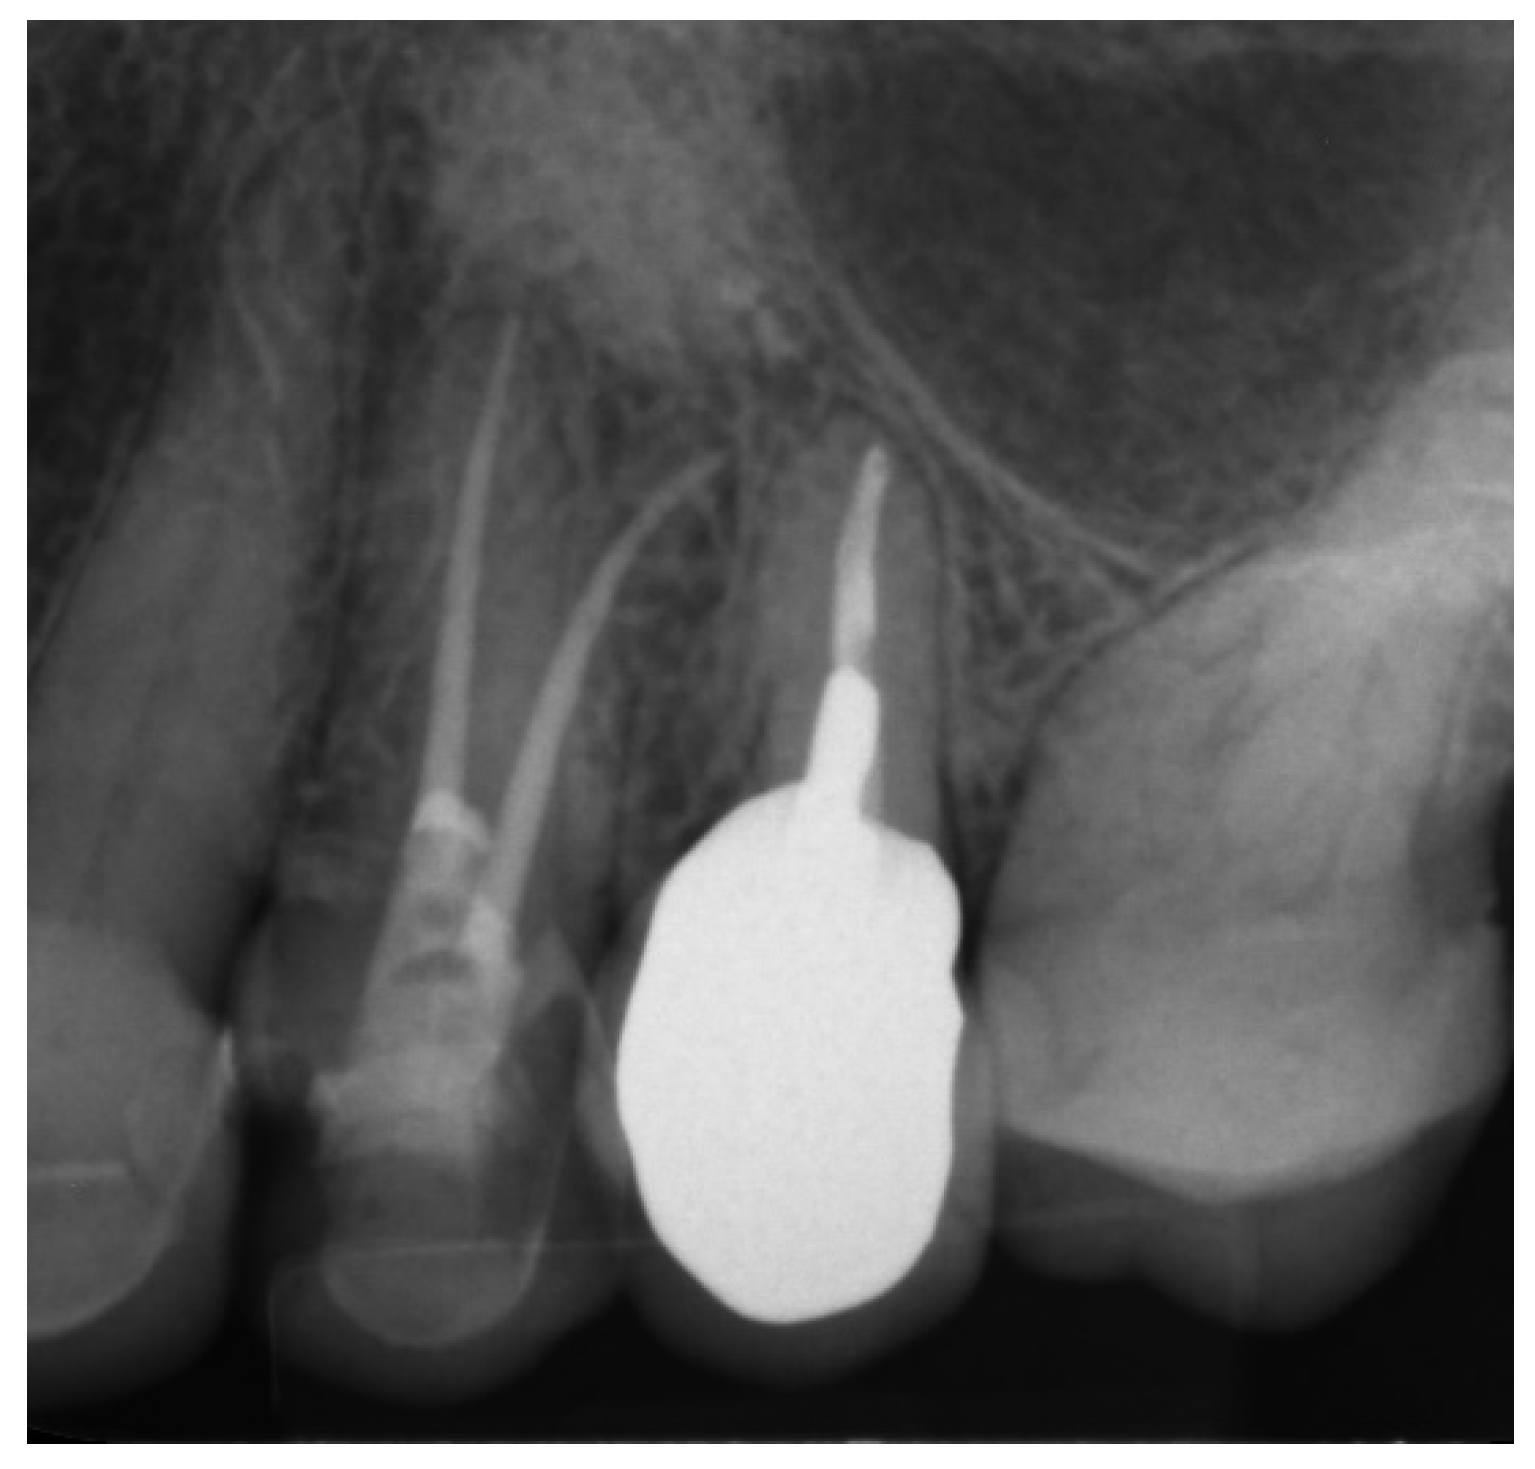

2.2.2. Case Report—Patient D: Symptomatic Pulp Necrosis with Pulp Canal Obliteration

A 68-year-old female patient reported to the endodontic specialist complaining of acute pain upon percussion of her maxillary first premolar (tooth 24), experienced for several days. The patient was healthy and did not have any general or chronic diseases. The clinical examination revealed tenderness to percussion and a negative response to the pulp sensibility test (cold test). Radiographic images revealed pulp canal calcification and the absence of the canal light (Figure 24). A CBCT scan was performed (CS 8100 3D, Carestream, 50 × 50 mm) and confirmed canal calcification (Figure 25). The palatal canal was found during the first visit. The buccal canal was obliterated. Due to the possible risk of higher tooth substance loss and perforation during endodontic access, we decided to perform the endodontic treatment with guided access.

Figure 24. X-ray image showing the obliteration of the root canal.

Figure 25. The CBCT image confirmed the calcification of the buccal canal.